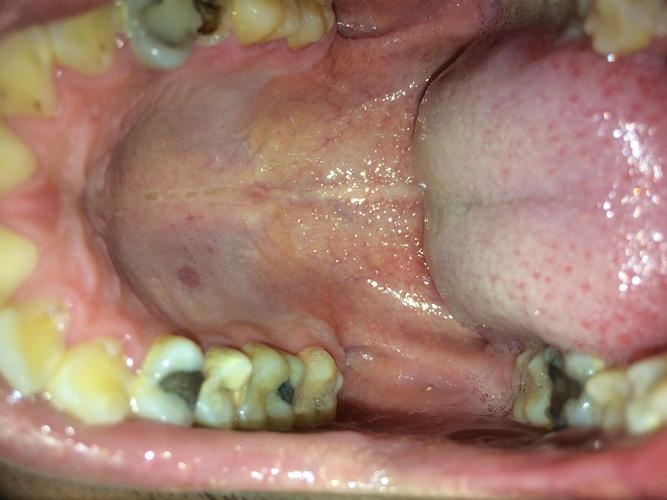

口腔上颚无痛硬块是何问题?

无痛的硬块,良性的可能性比较大,常见于以下几种情况:

口腔上颚的无痛硬块,绝大多数情况下是良性的粘液腺囊肿、腺样体增生或对刺激的正常反应。“无痛”并不等于“无害”,因为它也可能是某些严重疾病(如恶性肿瘤)的早期信号。